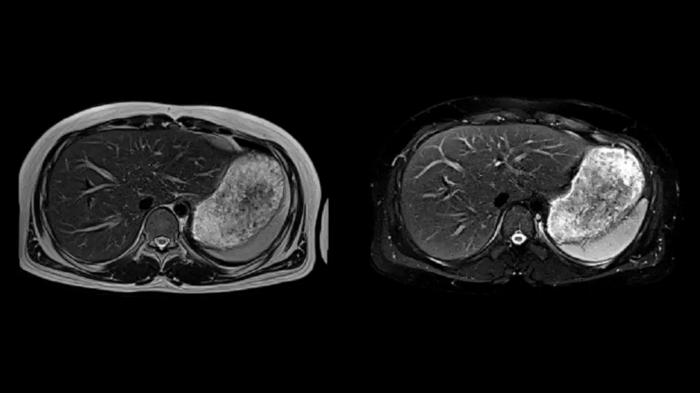

Abdomen

T1 VIBE Dixon with CAIPIRINHA

Get benefitted from Siemens Healthineers dedicated CAIPIRINHA acceleration to gain a complete abdominal volume within a single breath-hold. The Dixon technique offers outstanding fat water separation for a flawless representation of the abdominal anatomy.

Body diffusion imaging

For all-inclusive abdominal MR capabilities, outstanding quality diffusion imaging.

T2 BLADE

T2 motion insensitive abdominal imaging with BLADE results in outstanding outcomes, regardless of the orientation or if fat saturation is needed.